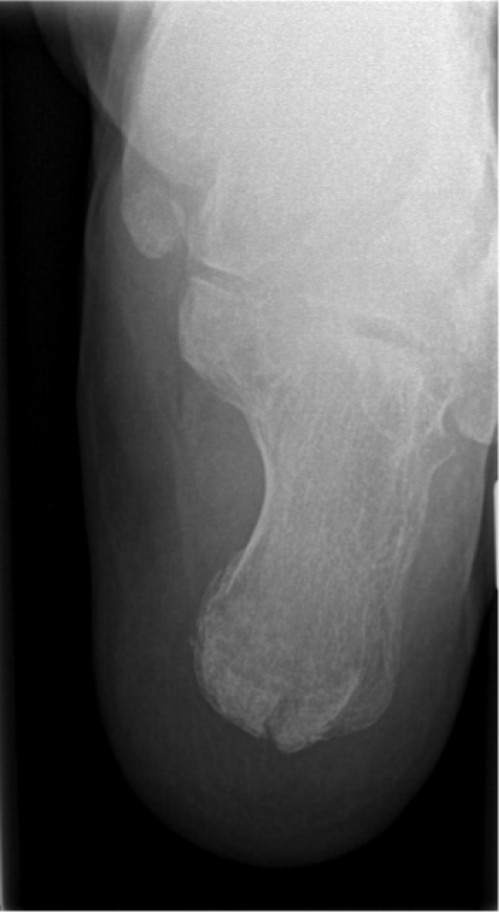

ICD: S82.5

ICD: S92.0

Eine 66-jährige Patientin stellt sich in der Notfallambulanz vor und berichtet von einer Leiter gestürzt zu sein. Sie habe für ihren Enkel Lego-Spielzeug vom Dachboden holen wollen und sei dabei von der Leiter gerutscht. Sie sei auf ihren beiden Fersen gelandet und anschließend auf den Rücken gefallen. Der linke Fuß sei seitdem nicht belastbar, der rechte Fuß schon. Am rechten Fuß sei jedoch eine Schwellung im Bereich der Sprunggelenke sichtbar geworden.